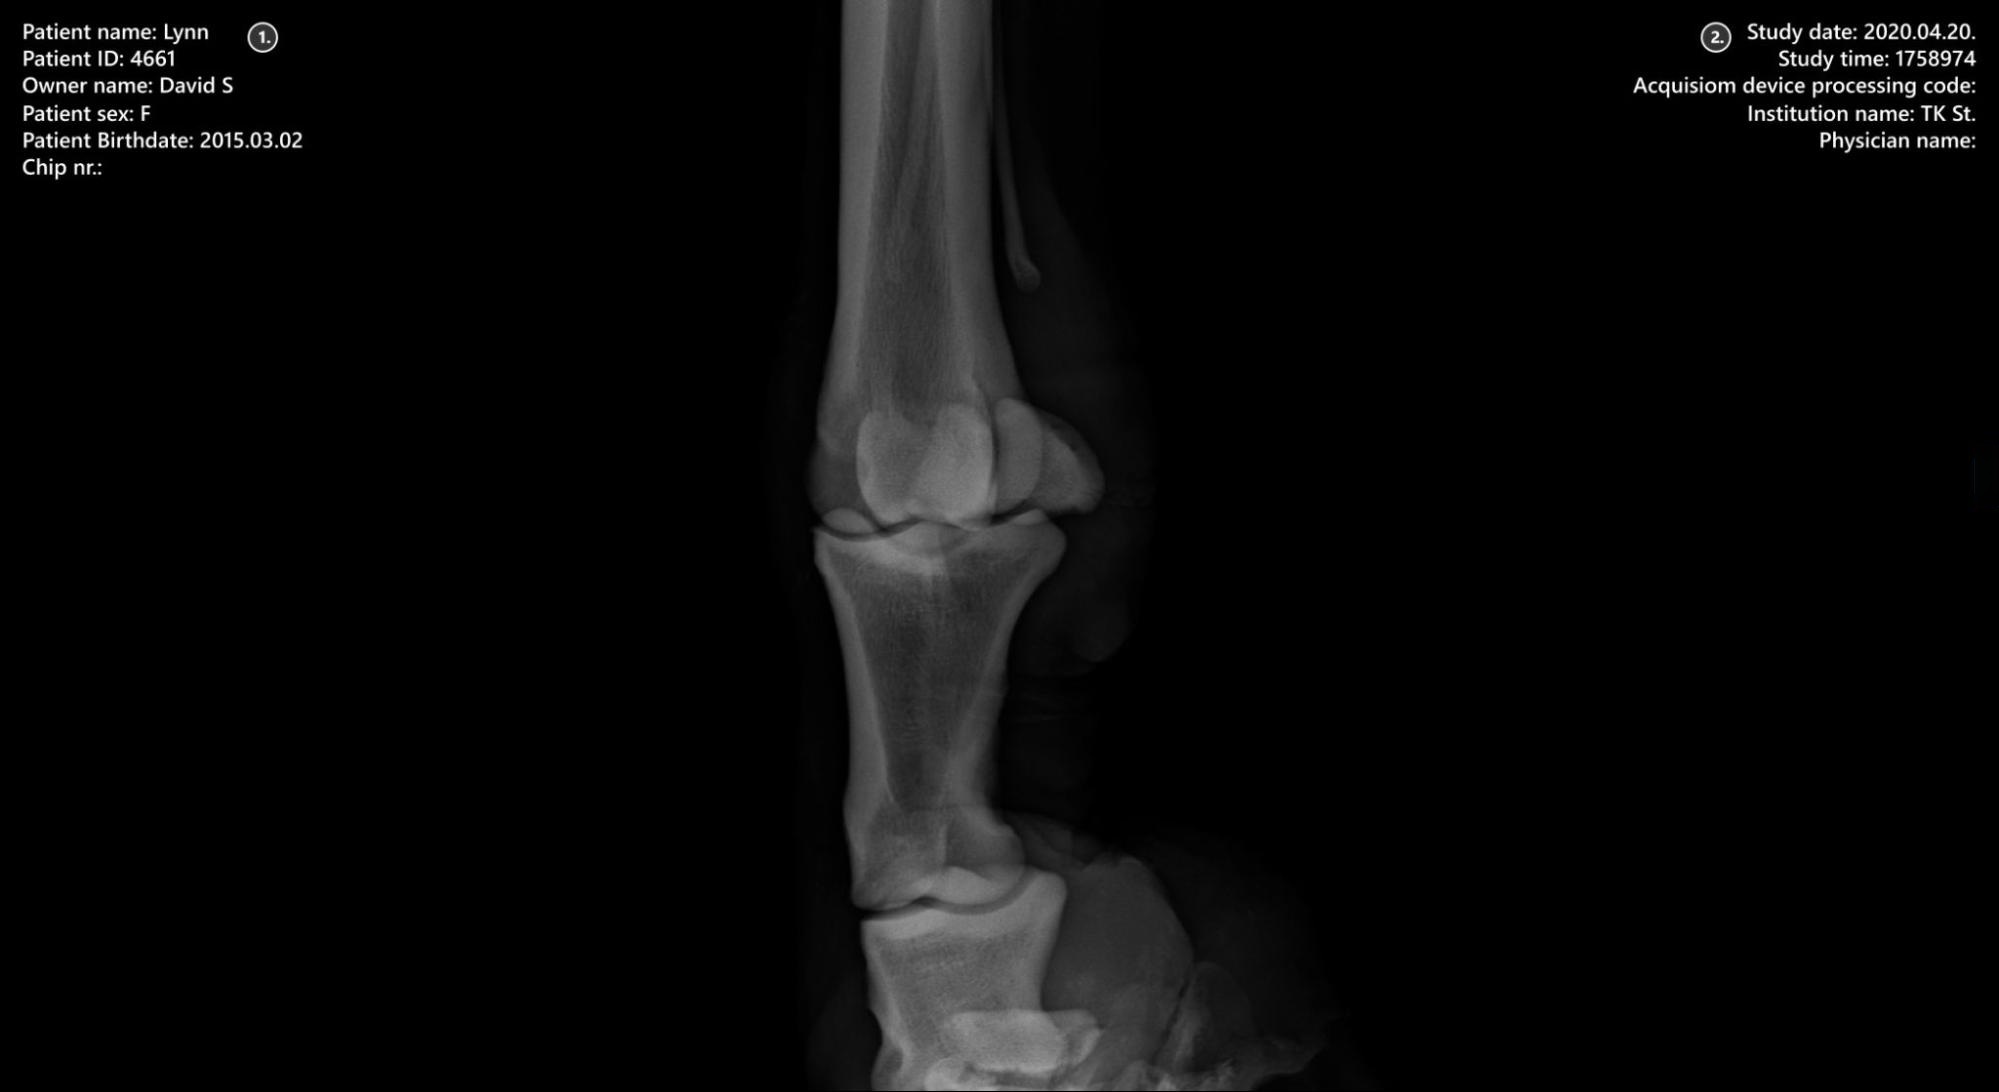

Viewer-Bereich¶

Patienteninformationen

Studieninformationen